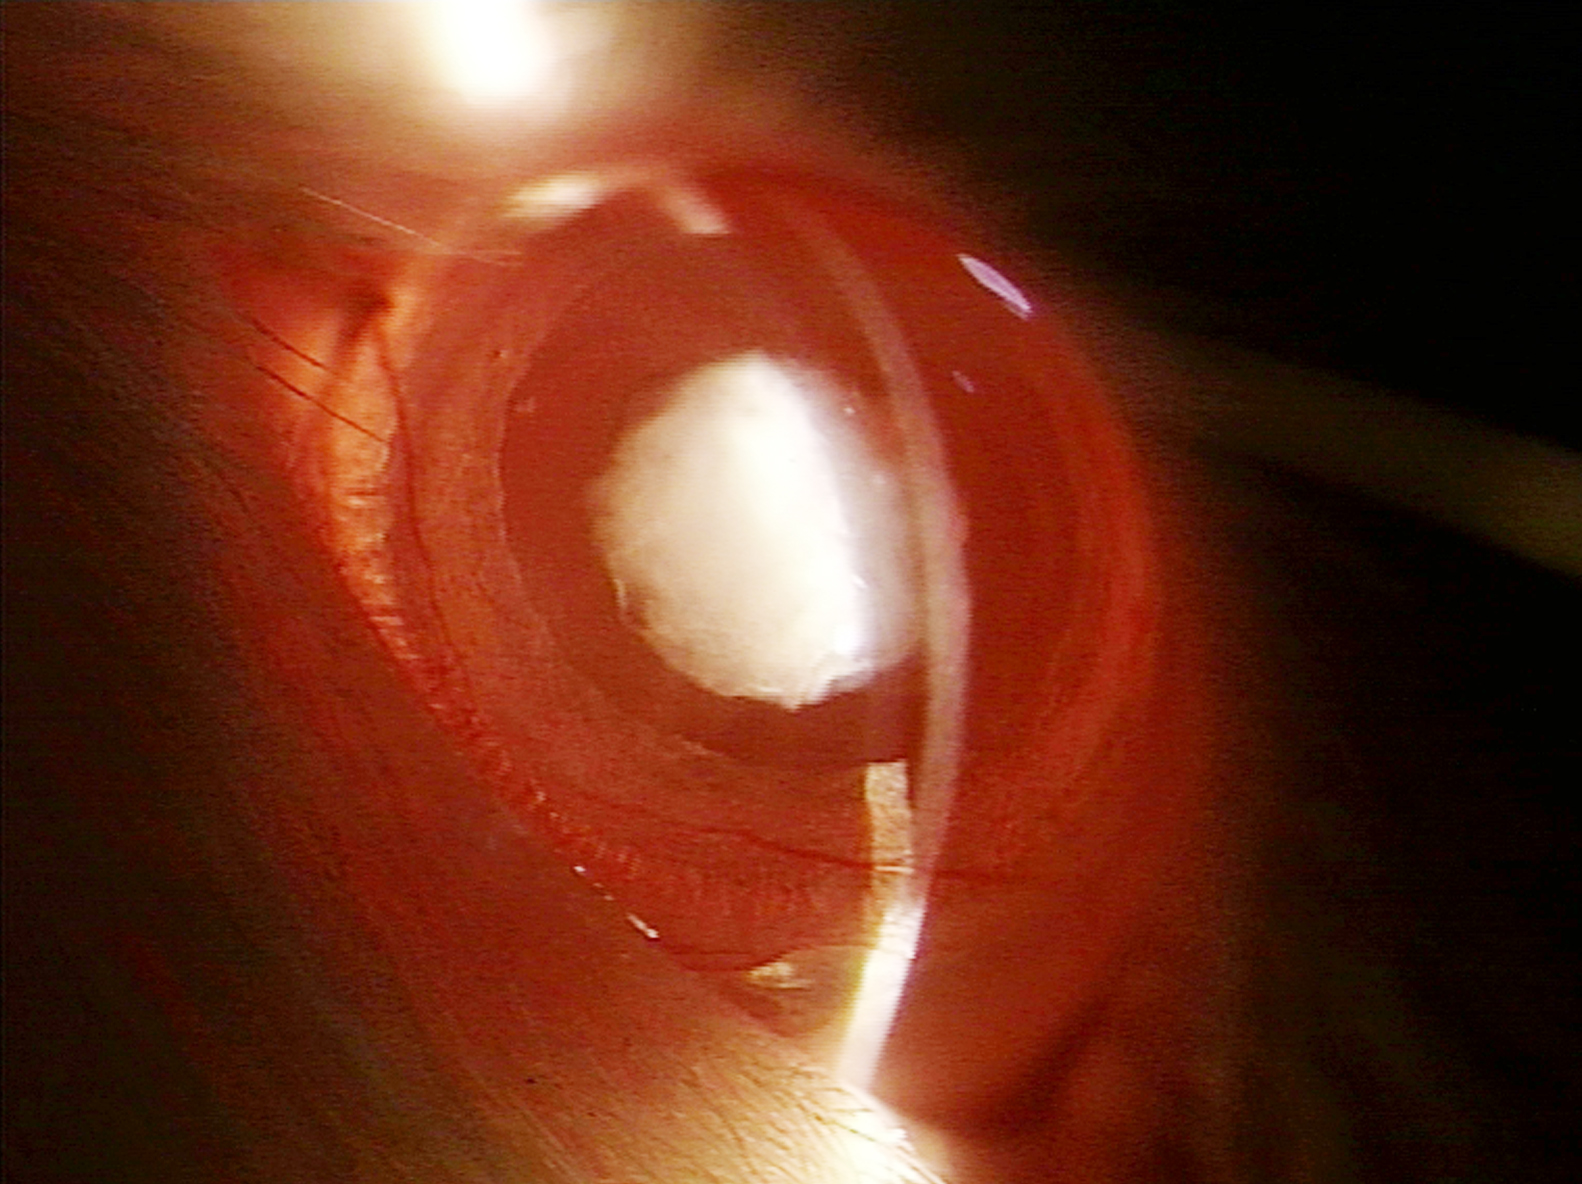

Figure 1 of Elanchezhian, Mol Vis 2009; 15:1485-1491.

Figure 1. Slit-lamp appearance of the eye of a 30-day-old Wistar rat pup in group II. The eye exhibited dense opacification of the lens (Grade +++ opacification).